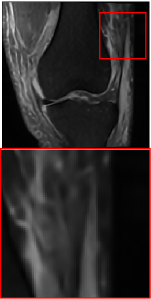

Public Dataset. The public dataset employed is the FastMRI Knee [43], where the reference contrast is PD, and the target contrast is FS-PD. We selected 1600 slices with a training, validation, and test set split ratio of 7:1:2.

Figure 5 provides the qualitative comparison of the various methods on the four datasets at a scale of 4. The top, second, third, and bottom rows are the SR results under the FastMRI, clinical brain, clinical tumor and clinical pelvic datasets, respectively. The red boxes indicate the zoom-in region of complicated anatomical structures along with their corresponding error maps. Note that the brighter textures in the error maps, the lower the quality of the reconstructed images. As can be seen, compared to methods based on Transformers and CNNs, diffusion-based methods like DisC-Diff and DiffMSR (Ours) are capable of reconstructing high-realistic images with promising reconstruction metric scores (PSNR and SSIM). Nevertheless, while DisC-Diff can reconstruct high-precision MR images, it does not preserve the structure present in the original HR images, introducing some additional information that can affect medical diagnosis. In contrast, our method combines DM and PLWformer, which can preserve the original image’s structure while restoring high-frequency information.